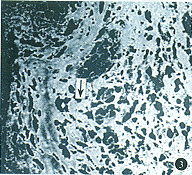

2.置线后应用IFNα-2b对瘢痕中胶原含量的影响:见表2。4.67×10-5μmol/L IFN α-2b无论是线下注射还是线旁注射均能降低其胶原含量(图3,4),与对照组相比,差异有非常显著性(P<0.01)。IFNα-2b同时能减少缝线周围结膜上皮、成纤维细胞及小血管内皮EGF受体表达(图5,6)。

图3,4 线下注射4.67×10-5 μmol/L IFNα-2b,可见对照组(图3)

胶原纤维减少(箭头示) Masson′s三色染色×500